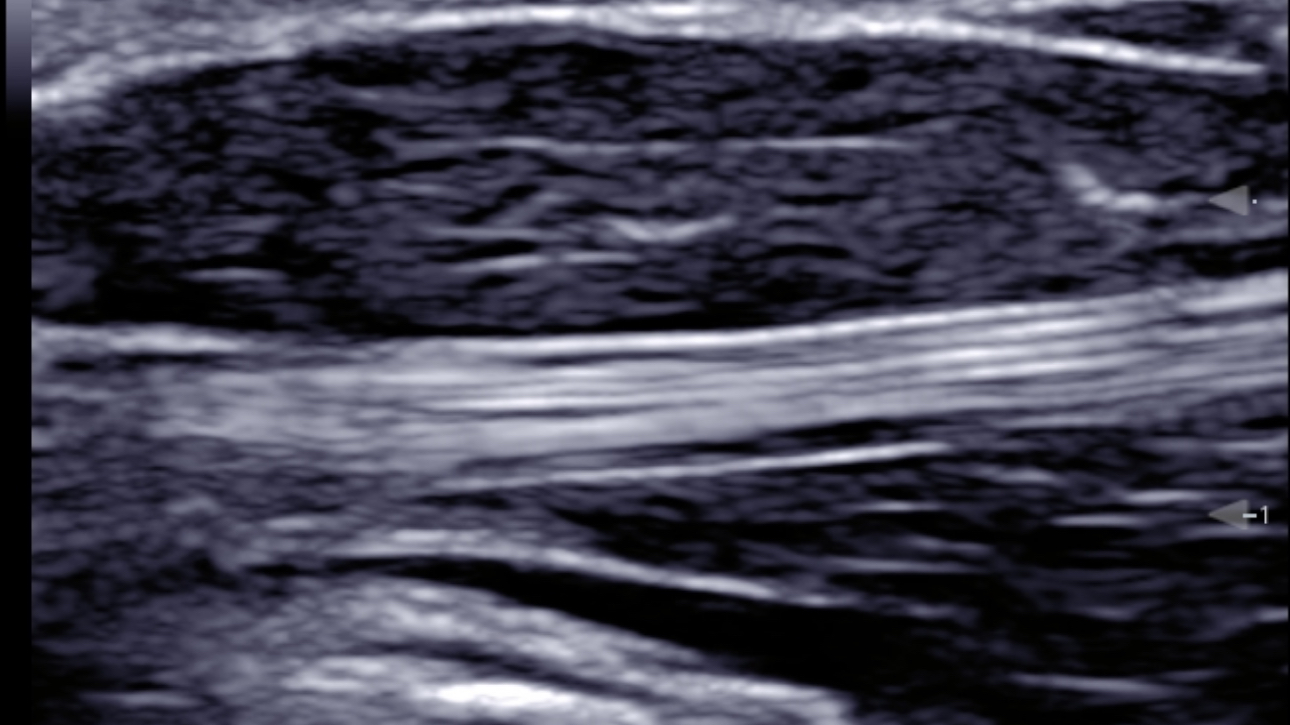

eSpacial Navi??and iNeedle+TM?ensure safe needling solution. Up to 20MHz ultra-high frequency linear transducer can visualize the finest nerves and fibers with extremely high resolution. Seamless monitor with full touch screen and exclusive clean-lock function ensure efficient cleaning and disinfection. The multiple modality design enables the TE5 to easily handle a wide range of medical scenarios.

Based on smart track of vessels, it can automatically optimize Color/Power and PW spectrum to reduce repetitive, time-consuming steps and simplify the vascular exam workflow:

- Real-time and automatically optimize Color box position & angle

- Real-time and automatically optimize PW sample volume position & angle & size